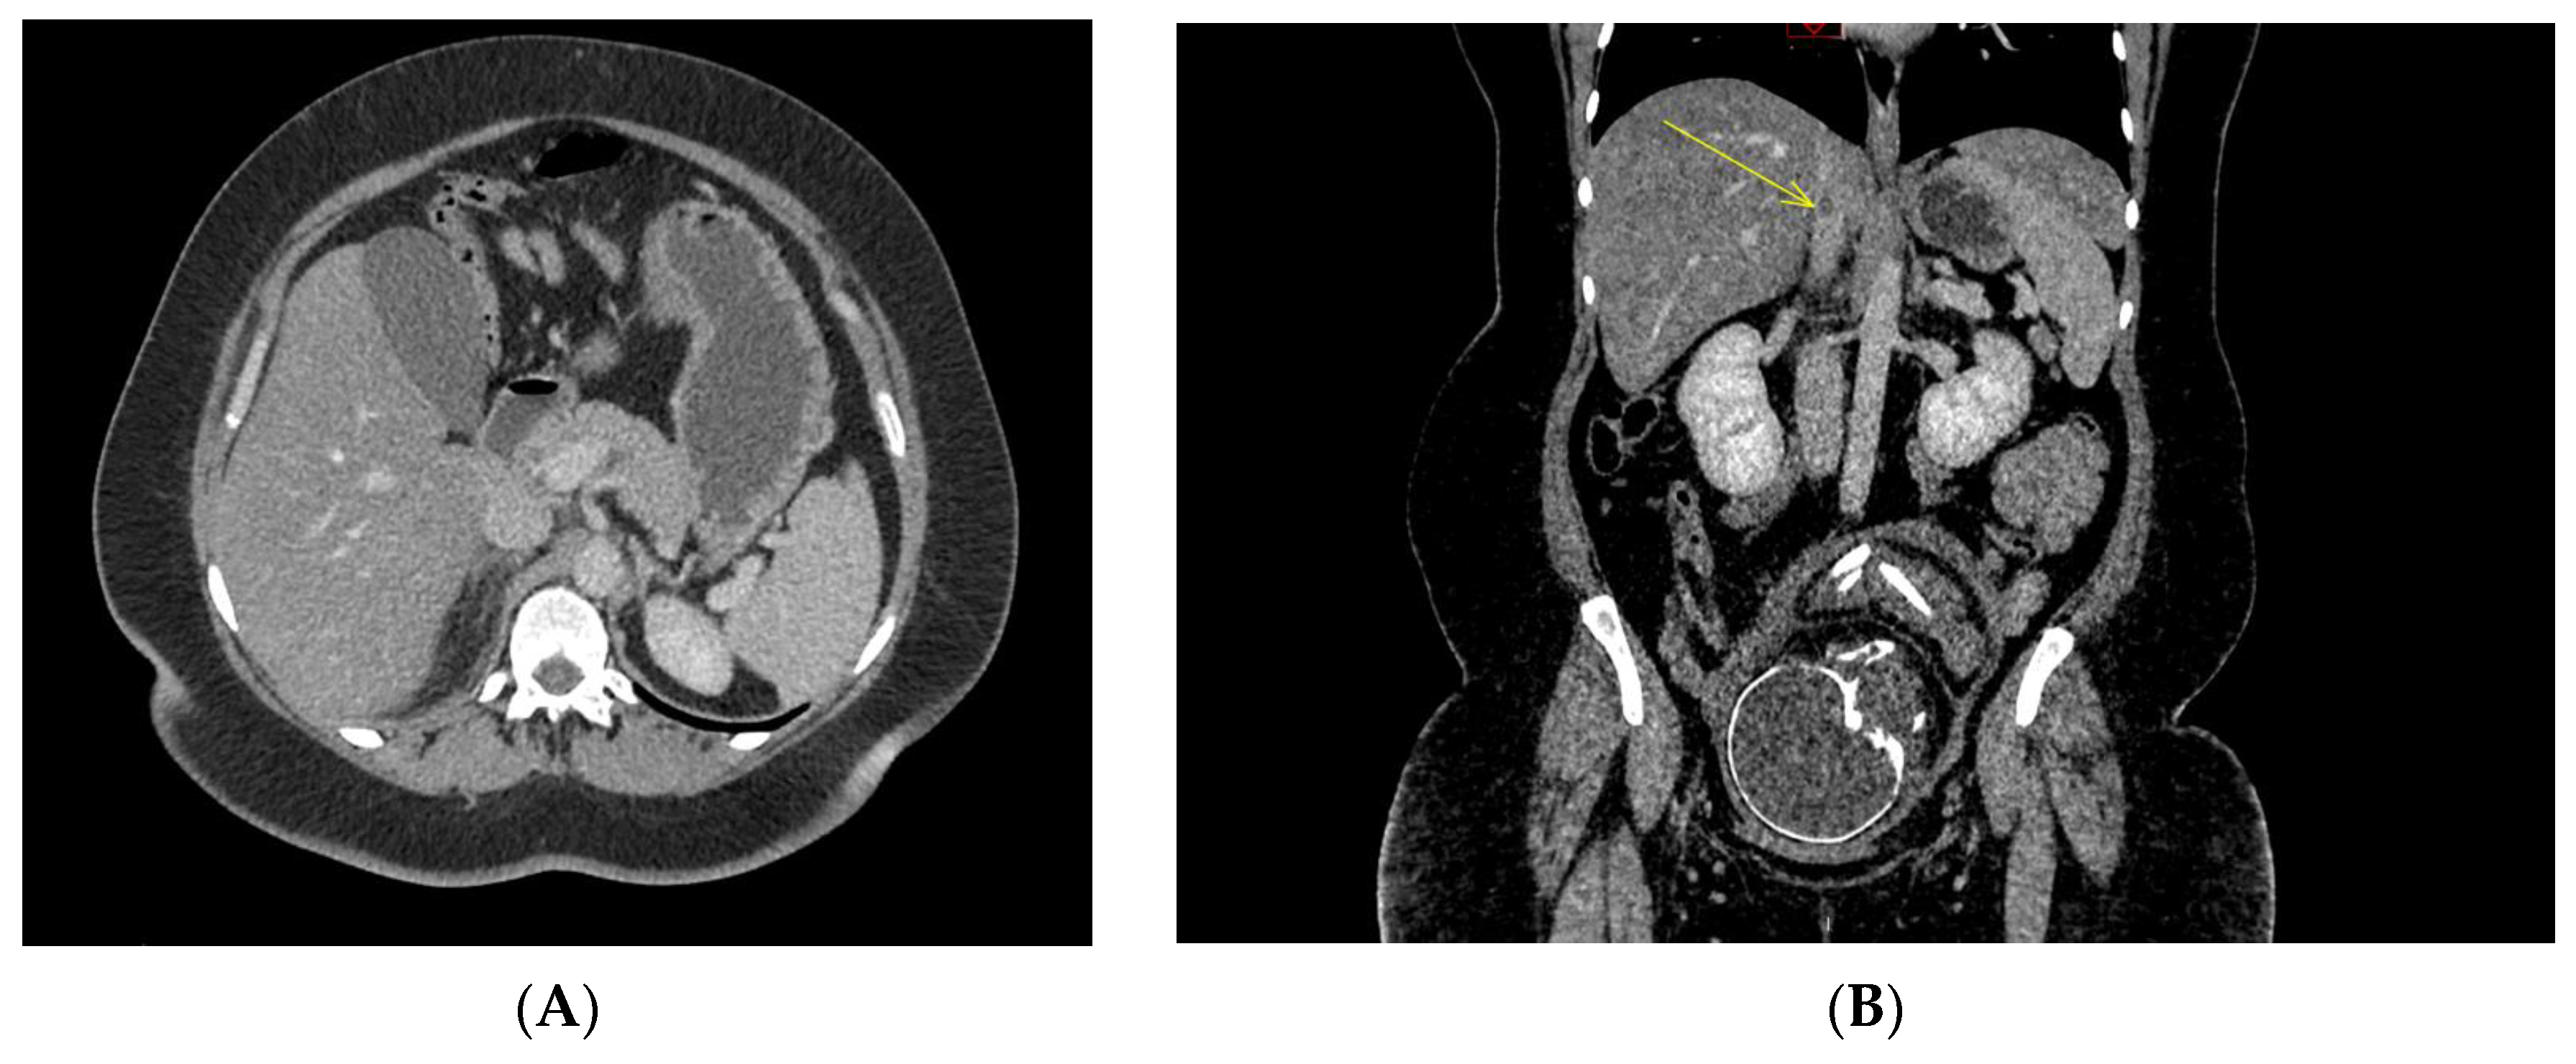

Concerning the radiological picture, all patients had the same assessment, namely an obstetrical ultrasound by the intern and/or the senior on-call obstetrical emergency, an abdominal ultrasound and an abdominopelvic or thoraco-abdominopelvic CT scan. The obstetrical ultrasounds were all reassuring. Abdominal ultrasounds were normal or noncontributory for all cases. The computed tomography scans made it possible to diagnose adrenal glands necrosis. (Figure 2). There are seven necroses of the right adrenal gland in one case of bilateral involvement. There were six cases of nonhemorrhagic necrosis and two cases of adrenal gland hemorrhagic necrosis. Thrombosis, of the adrenal vein or the inferior vena cava, was not always visualized. The mean time to diagnosis at the Nantes University Hospital was 18 h.

Concerning the imaging modalities, the contrast-enhanced CT is considered the gold standard imaging modality to rule out an adrenal ischemia. However, MRI is preferred over CT in pregnancies earlier than 25 weeks to protect of ionizing radiation and iodinated contrast material. Specific CT signs help to make the diagnosis without delay: spontaneous hypodensity and hypertrophy of the adrenal gland, slight enhancement after injection of contrast, periadrenal fatty infiltration, the “capsular sign” known as a hyperdense subtle peripheral line around a hypodense adrenal gland which is 100% specific of an early phase of adrenal ischemia and, less frequently, thrombosis of the adrenal vein; thrombosis might be extended into the lower vena cava and can be associated with iliac and pelvic veins thrombosis [23]. MRI features with morphologic abnormalities included unilateral adrenal enlargement, increased T2 signal intensity of the infarcted land with surrounding retroperitoneal edema and without T1 signal intensity suggesting hemorrhage [1].

Figure 2. CT-scan sections ((A) infiltration of the right adrenal compartment with edematous appearance and overall hypo-enhancement of the right adrenal gland; (B) yellow arrow indicates venous thrombosis of the inferior vena cava complicated by hemorrhagic necrosis of the right adrenal gland).